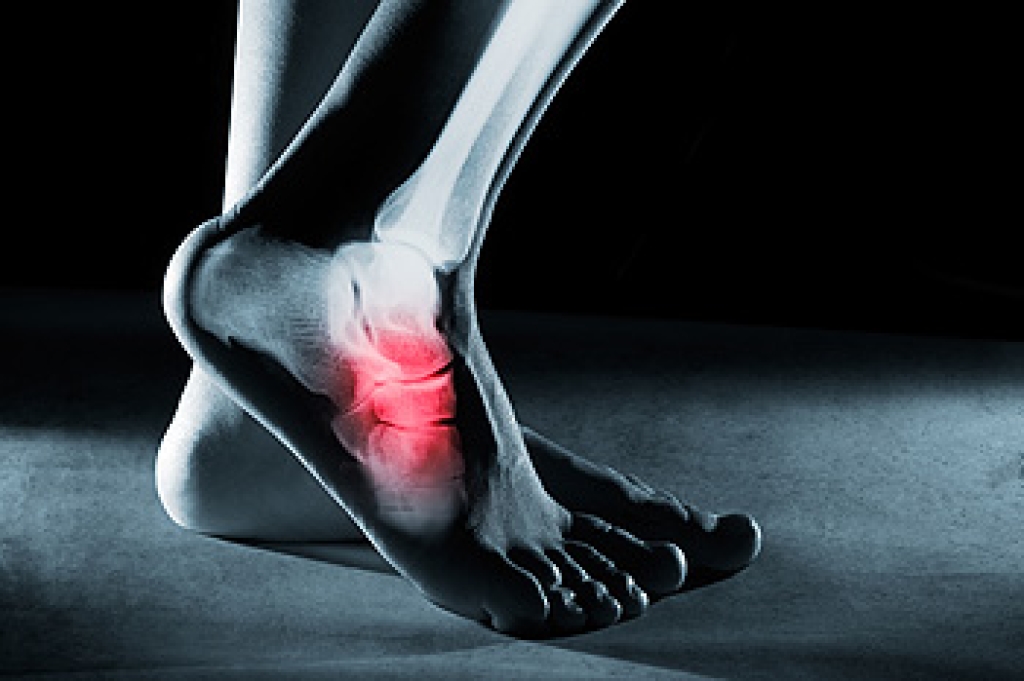

Dealing with Stress Fractures of the Foot and Ankle

Stress fractures occur in the foot and ankle when muscles in these areas weaken from too much or too little use. The feet and ankles then lose support when walking or running from the impact of the ground. Since there is no protection, the bones receive the full impact of each step. Stress on the feet can cause cracks to form in the bones, thus creating stress fractures.

What Are Stress Fractures?

Stress fractures occur frequently in individuals whose daily activities cause great impact on the feet and ankles. Stress factors are most common among: